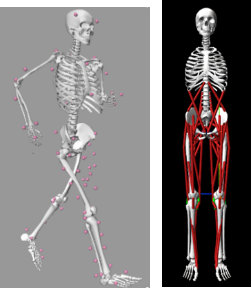

(2) Computational Biomechanics 计算生物力学

FEM 有限元

Contact Analysis 接触分析

Inverse/Forward dynamics 逆向动力学/正向动力学

图注:FEM 有限元分析、力动学分析、骨与关节数字建模

图注:逆动力学分析